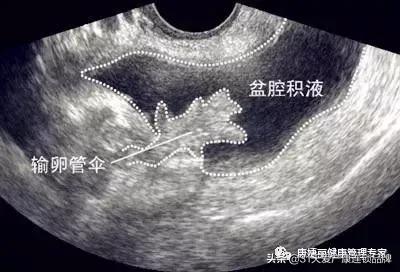

盆腔积液是指对盆腔内液体这一表现的一种描述。可分为生理性盆腔积液和病理性盆腔积液。先来说说生理性盆腔积液。

盆腔处于腹腔最低部,当盆腹腔脏器有少量渗出液、漏出液时,液体会先聚积在盆腔,从而形成盆腔积液。

这里主要指卵巢黄体出血、卵巢囊肿破裂等。就如同盆腔里放着一个充满水的气球,由于特殊的情况气球破裂,里面的水流到了盆腔里。另外,宫外孕破裂会导致大量血液流出,导致盆腔积液现象。